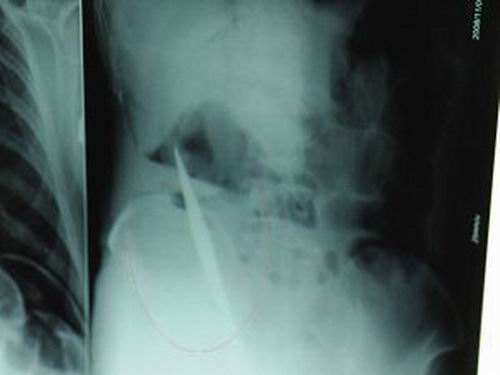

X光片上,尖刀清晰可见。

从男子体内取出的尖刀足足有19厘米长。

昨天(11月6日)上午,记者在徐州矿务集团总医院重症监护室见到了这名男子,目前他虽然已经恢复了意识,但还不能开口说话,需要呼吸机辅助呼吸。据医生介绍,4日中午12时左右,这名男子因服毒轻生被紧急送到医院进行抢救,之前,这名男子已经在当地乡镇医院进行了近20小时的治疗,但效果不佳。“病人被转院到矿总院时已神志不清,血压极低,处于休克状态。”救护人员给男子洗胃、初步处理以后,发现男子呼吸急促,于是赶紧给他拍片检查。结果让所有的医生大吃一惊,竟有一把尖状异物横在该男子腹腔内!当天下午5时30分,轻生男子被推上了手术台。经过40多分钟的手术,该男子腹腔被打开,手术医生发现,男子体内的金属状异物竟然是一把长19厘米的尖刀!

医生告诉记者,手术后,医生在病人身上并未发现刀痕,最后,经过检查发现,在该男子直肠处找到穿孔。医生从医学角度分析后认为,这把尖刀应该是从肛门插入直肠的。